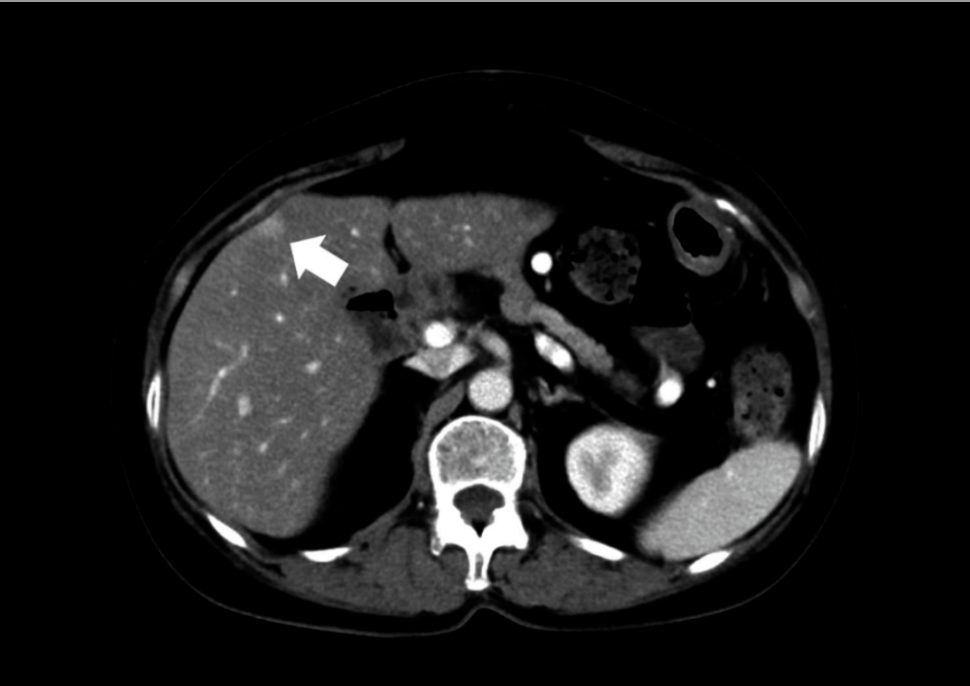

肝切除术后2个月,患者因肺脓肿(图4)再次入院,病灶位于肝切除部位邻近右肺区域。

图4. 病例2再次入院时CT显示右肺邻近肝切除部位含气液平面病灶(箭头)

经抗生素治疗后病灶改善,考虑为肝断面脓肿继发。保守治疗后好转,术后10天无并发症出院。术后9个月无复发存活。